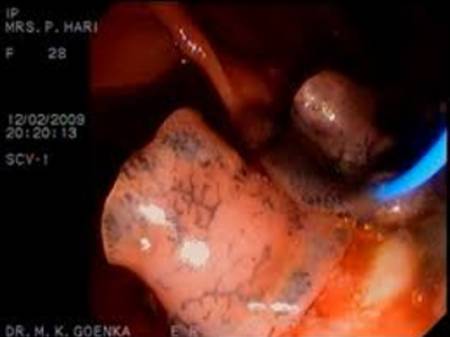

Trường hợp thứ ba: Một phụ nữ 49 tuổi người Cáp-ca với bệnh sử đau bụng và có triệu chứng trào ngược dạ dày thực quản 12 tháng nay (gastroesophageal reflux). Bệnh nhân đã đi du lịch nhiều nơi ở Đông Nam Á với thời gian dài 18 tháng trước khi nhập viện nhưng không ăn các loài nhuyễn thể hoặc những món thịt chưa chế biến kỹ (non-kosher meat). Sinh thiết dạ dày thông qua nội soi đường tiêu hóa trên cho kết quả viêm dạ dày tăng bạch cầu eosin (eosinophilic gastritis), lượng bạch cầu ái toan là 0.95 x 109/L, xét nghiệm huyết thanh học với Gnathostoma dương tính. Triệu chứng bệnh thuyên giảm dần và khỏi hẳn sau khi điều trị phác đồ albendazole.

H14

Trường hợp thứ tư: Một phụ nữ 30 tuổi có triệu chứng đau bên đùi trái trong khi cô ta tham gia vào một cuoc chay đua Eco-Challenge 2000 ở Borneo, xuất hiện một nốt, cục kích thước 4x3cm ở vùng đùi trái đã góp phần làm đau xé cơ của bệnh nhân; cục này tồn tại 12 tháng và sau đó cô ta phải nhập viện bệnh viện nhiệt đới London. Chụp cộng hưởng từ (MRI) ở đùi cho thấy một tổn thương phân thùy (lobulated lesion) bên trong bó cơ lớn, xung quanh có phù. Kết quả chẩn đoán huyết thanh học với Gnathostoma dương tính. Điều trị liệu trình 21 ngày bằng albendazole cho thấy có giảm dần kích thước tổn thương nhưng không hết hẳn hoàn toàn.